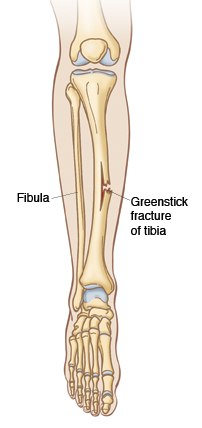

What type of fracture is this? What patient demographic is it most common in?

Greenstick fracture: occurs when a bone bends and cracks, instead of breaking completely. The fracture looks similar to what happens when you try to break a small, “green” branch on a tree.

Most occur in children younger than 10